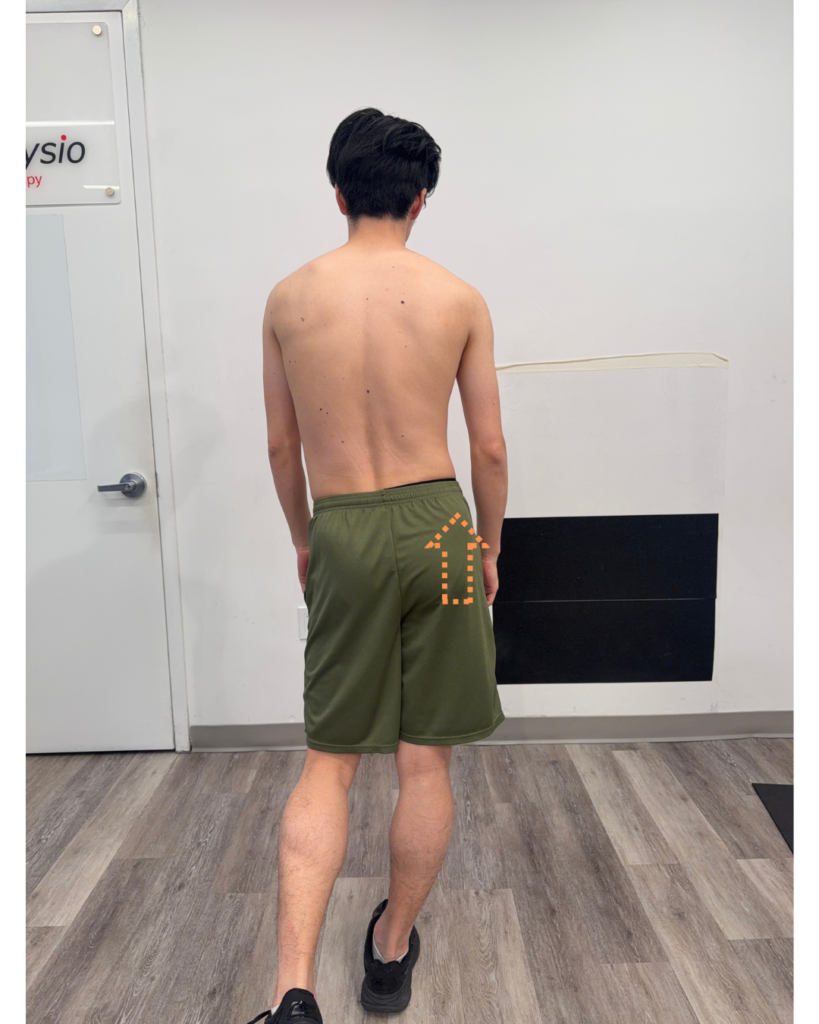

(pelvic drop on the swing side)

(pelvic hike on the stance leg)